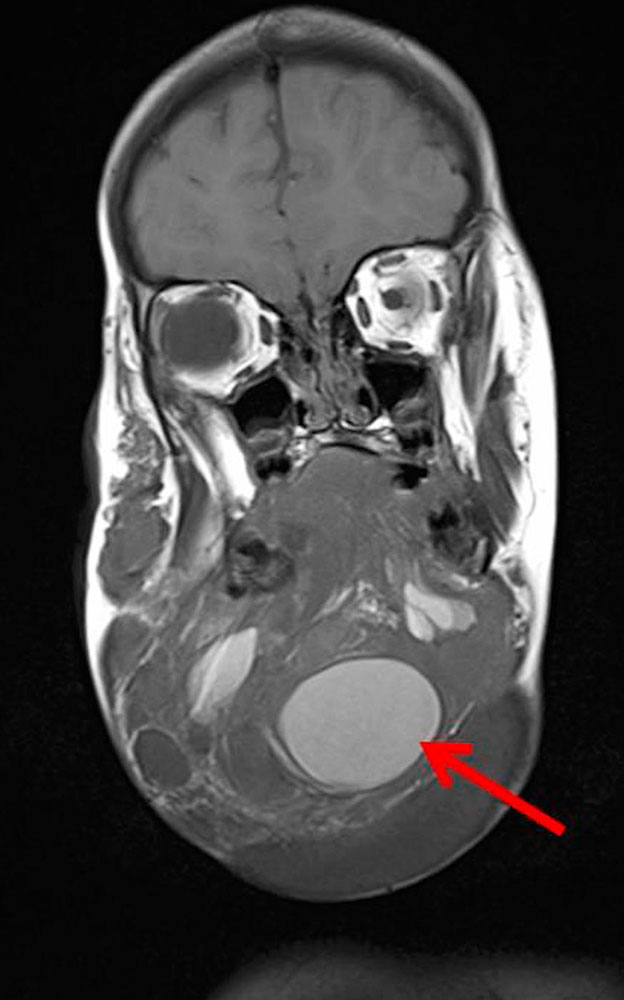

Gerade makrozystische LM können akut einbluten, wahrscheinlich über Kommunikationen mit dem venösen System, das embryologisch nah verwandt ist und immer mit dem Lymphgefäßsystem kommuniziert. Eine akute Einblutung führt zu einer akuten Vergrößerung der Zyste mit schnell zunehmender Raumforderungswirkung. Die Zyste schmerzt dann akut und ist verhärtet. Gerade im Halsbereich kann dies dramatische Konsequenzen auf die oberen Luftwege haben.